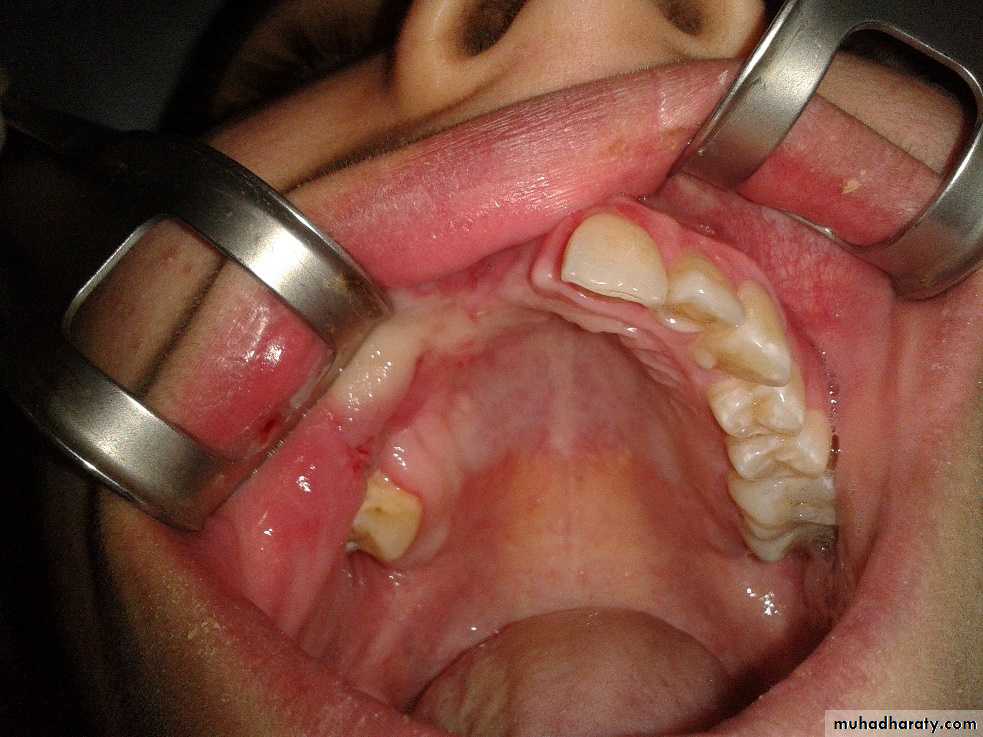

2.Fiber osteoma or (ossifying fiberoma ) :

which is a benign slow growing tumor of bone that tends to have its greatest growth in the second decade of life. it is a diffuse poorly differentiated endosteal tumor. replacing the normal spongiosa with fibrous tissues. The enlargement neoplasm may displace teeth and expand cortical plates of the jaw bones.Fibro-osteoma tends to occur more frequently in women than in man and is seen more often in the maxilla than in the mandible. The active fibro-osteoma or ossifying fibroma frequently recurs when surgical excision dose not include . 10 to 12mm margin or when treatment has been instituted at an early age. radical treatment is less likely to lead to a later recurrence. These tumors do not respond favorably to radiation therapy.